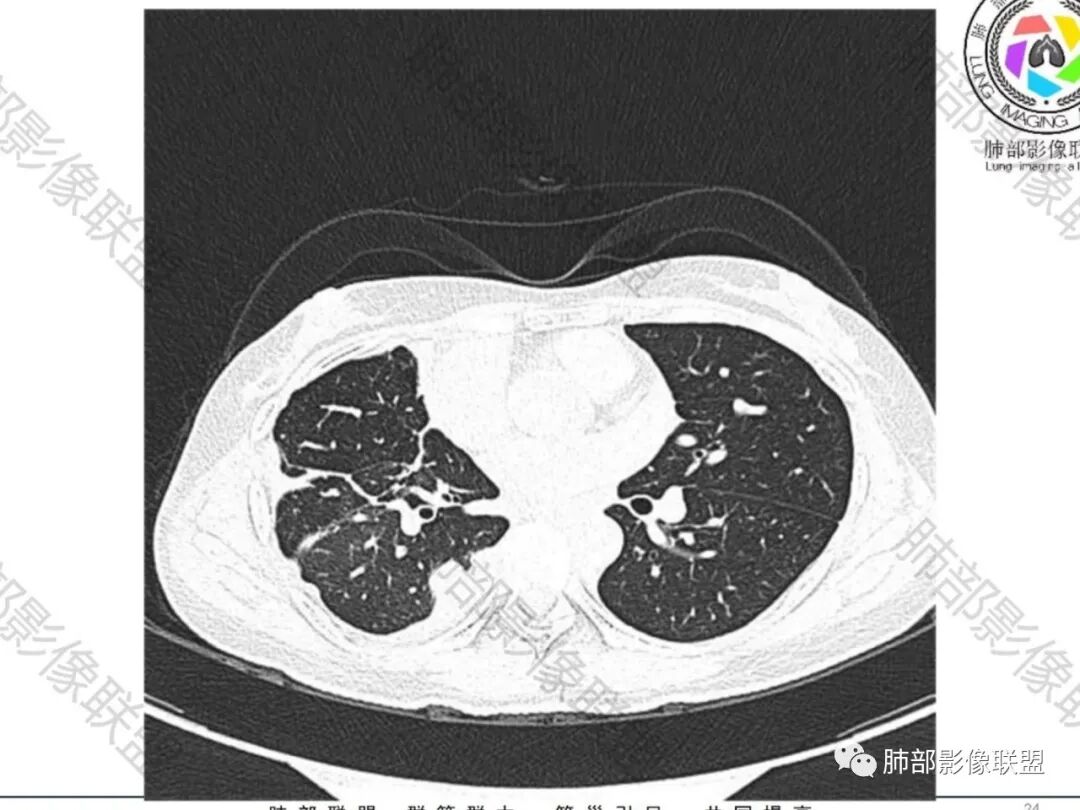

丽:双肺散在索条及条片状高密度影,边界清晰,部分实变内可见钙化,支气管管壁增厚,双肺胸膜局限性增厚伴钙化,部分肋骨密度增高,首先考虑结核并淀粉样变性,鉴别转移性钙化,肿瘤样钙质沉着症,胸膜间皮瘤。

尘缘:青年女性,痰中带血,胸痛2月,无发热盗汗,实验室检查,有贫血,总蛋白降低,血沉情况未知,肿标基本正常。影像表现:双上肺小叶间隔增厚,双侧胸膜广泛不规则增厚,胸膜下多发肿块伴不规则钙化,右侧肋骨破坏。纵隔淋巴结肿大不明显,双肺门淋巴结肿大,部分融合,分析思路:一、感染性病变,1、结核,青年女性,胸膜增厚,多发肿块伴钙化,有咳嗽胸痛,痰中带血,要考虑,但无结核中毒症状,病史仅两月却钙化太明显,肺内没有明显树芽征,存疑,2、其他感染,无炎性指标支持,白细胞不高,可能性小。二、非感染性病变,1、尘肺,胸膜增厚,钙化,胸膜下钙化性肿块,要考虑,但肺内无粉尘结节,无职业史,可能小。2、转移性钙化,无肾脏病史,无血清钙磷代谢异常指标支持,肺内间质无钙沉积改变,基本排除。三、肿瘤性病变,1、肺癌伴转移,双上肺有小叶间隔增厚,双肺门有淋巴结肿大,要考虑,但青年女性,病史两月,钙化太多太广泛,肿标基本正常,可能性小。2、骨肉瘤转移。15-30岁青年人,是骨肉瘤高发年龄,肺内多发成骨样钙化转移灶,双上肺小叶间隔增厚符合癌淋样表现,右侧肋骨破坏,要高度怀疑,需要详细询问病史及手术史。3、软骨来源肿瘤伴肺内转移,右侧肋骨虽有破坏,但无明显软骨样破坏及钙化。可能小。4、其他肿瘤伴转移,青年女性,其他恶性肿瘤能广泛发生钙化性转移的可能性小。综上所述:骨肉瘤伴右侧肋骨及胸膜转移,胸膜下转移,肺内癌淋可能最大,结核不完全除外,下一步需要,仔细询问病史,如果有骨肉瘤史,则基本确诊,如果没有,需要进一步问询呼吸系统症状,病程,以前的影像对照,了解肾脏情况,查血清钙磷指标。

空洞形成,一般伴随的很多都是气道的播散,树芽征

这个病例没有

空洞内壁算光滑,但是外侧的壁结节过于突兀